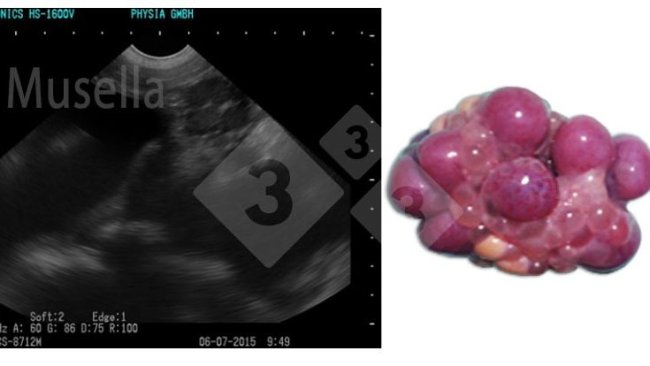

Artigos sobre ecografia